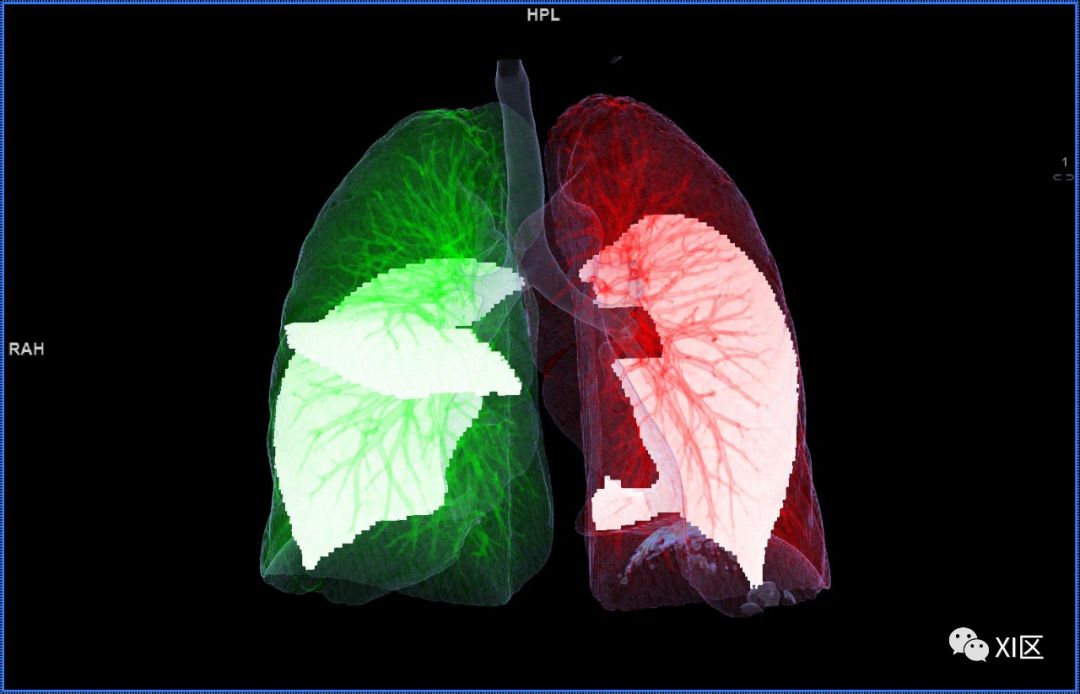

肺表面重建显示叶间裂和肺的分叶

透视图显示肺的叶间裂和肺的分叶

气管树与左右肺的关系